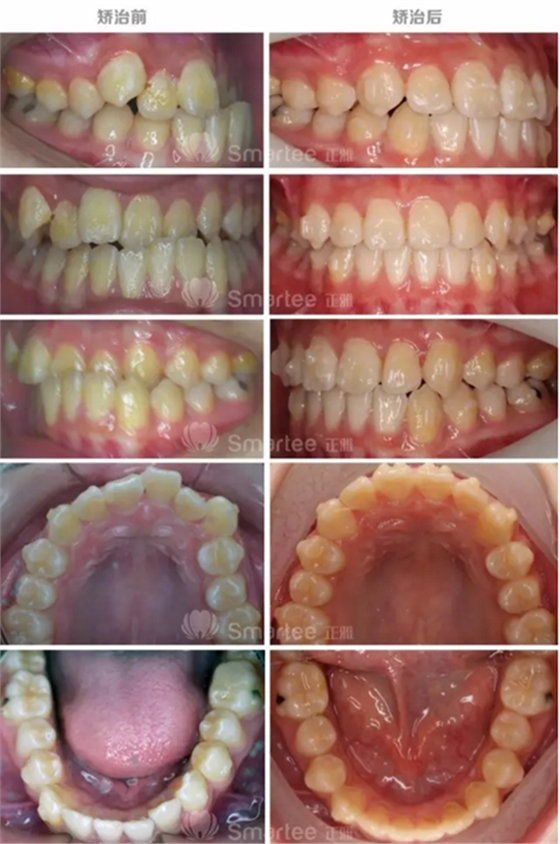

(矯治前后反饋情況對比)